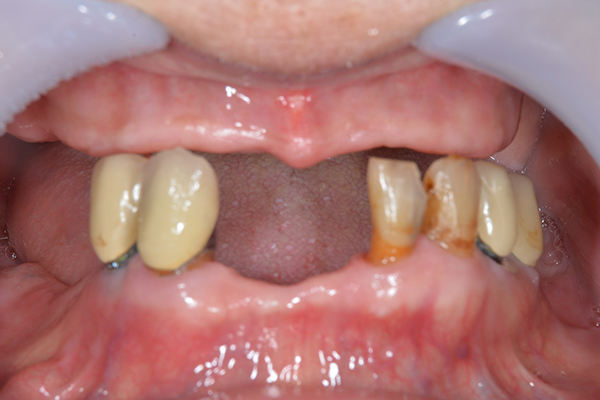

ケース1(自費の部分入れ歯)

前歯が折れて当院にいらっしゃいました。 過去に下の入れ歯を作ったが、合わなくなってずっと入れ歯をいれていらっしゃらない患者様でした。 これは奥歯で噛むことができないため、前歯で噛むことを繰り返したために、負担に耐えられなくなった前歯が折れてかぶせ物ごと 外れてしまったのだと考えられます。 痛くない、違和感の少ない、下の入れ歯を作ることがこの方のゴールであると考えられました。

金属を使用して、薄く違和感が少ない入れ歯が完成しました。 また、見た目にも気を使い、バネが見えにくい様な構造にしました。

入れ歯をお口の中にいれた状態です。前歯もMTMといって、歯を少し引っ張り出す処置を行なったことで、しっかり残せて、またかぶせ物をしました。